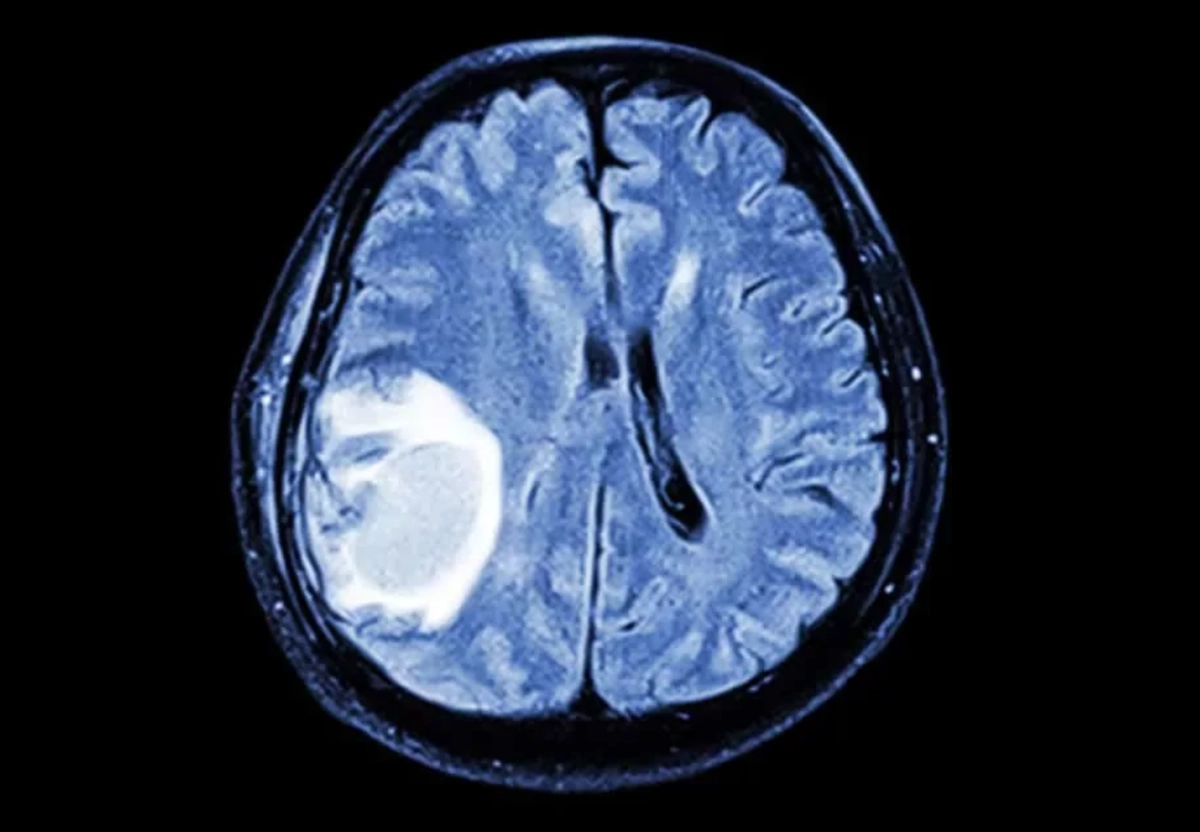

Опухоль в человеческом теле может вырастить зубы